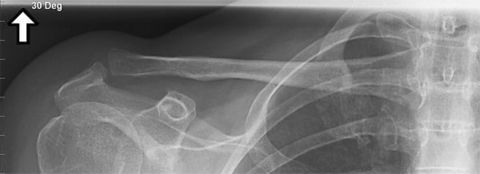

| AP Shoulder internal rotation | the MCP is tilted posteriorly as marked by the superior scapular angle is inferior to the clavicle |

| AP Shoulder | patient is rotated towards the unaffected shoulder: decreased thoracic superimposition over the scapular body |

| AP Shoulder | patient is rotated towards affected side:increased thoracic superimposition over the scapular body |

| AP Shoulder Neutral | ANATOMY: proximal humerus, lateral 2/3 of clavicle, open shoulder joint CRITERIA: humeral epicondyles are 45 degrees to the IR neither tubercle should be seen on the humeral head POSITIONING: CR perpendicular @ 1'' inferior to coracoid process |

| AP Shoulder Internal Rotation | CRITERIA: lesser tubercle in profile medially POSITIONING: CR perpendicular @ 1'' inferior to coracoid process |

| AP Shoulder External Rotation | CRITERIA: greater tubercle in profile laterally POSITIONING: CR perpendicular @ 1'' inferior to coracoid process |